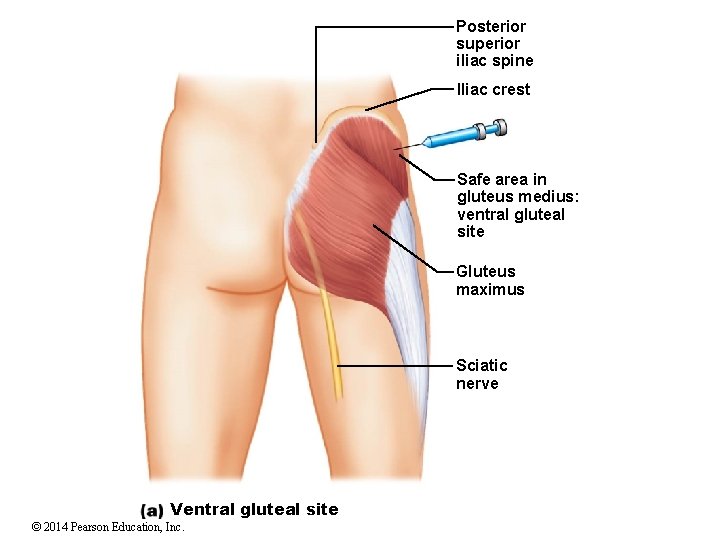

Posterior superior iliac spine Iliac crest Safe area in gluteus medius: ventral gluteal site Gluteus maximus Sciatic nerve Ventral gluteal site © 2014 Pearson Education, Inc.